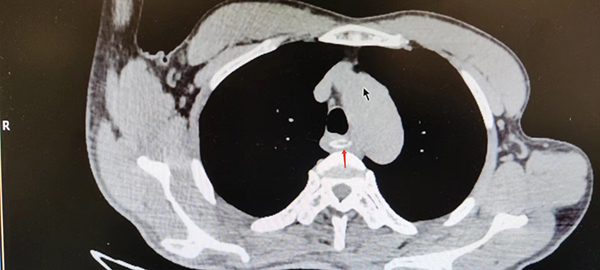

胸部CT照片(红色箭头指向异物处)

了解情况后,消化内镜中心副主任何玉琦翻阅了患者的胸部CT,决定先用胃镜检查一探究竟。结果这不查不知道,一查之后真吓一跳,整个牛骨头横跨在食管腔内,把食管堵了个严严实实,而且两端非常锐利垂直穿入食管两侧壁内,极有可能存在食管穿孔。